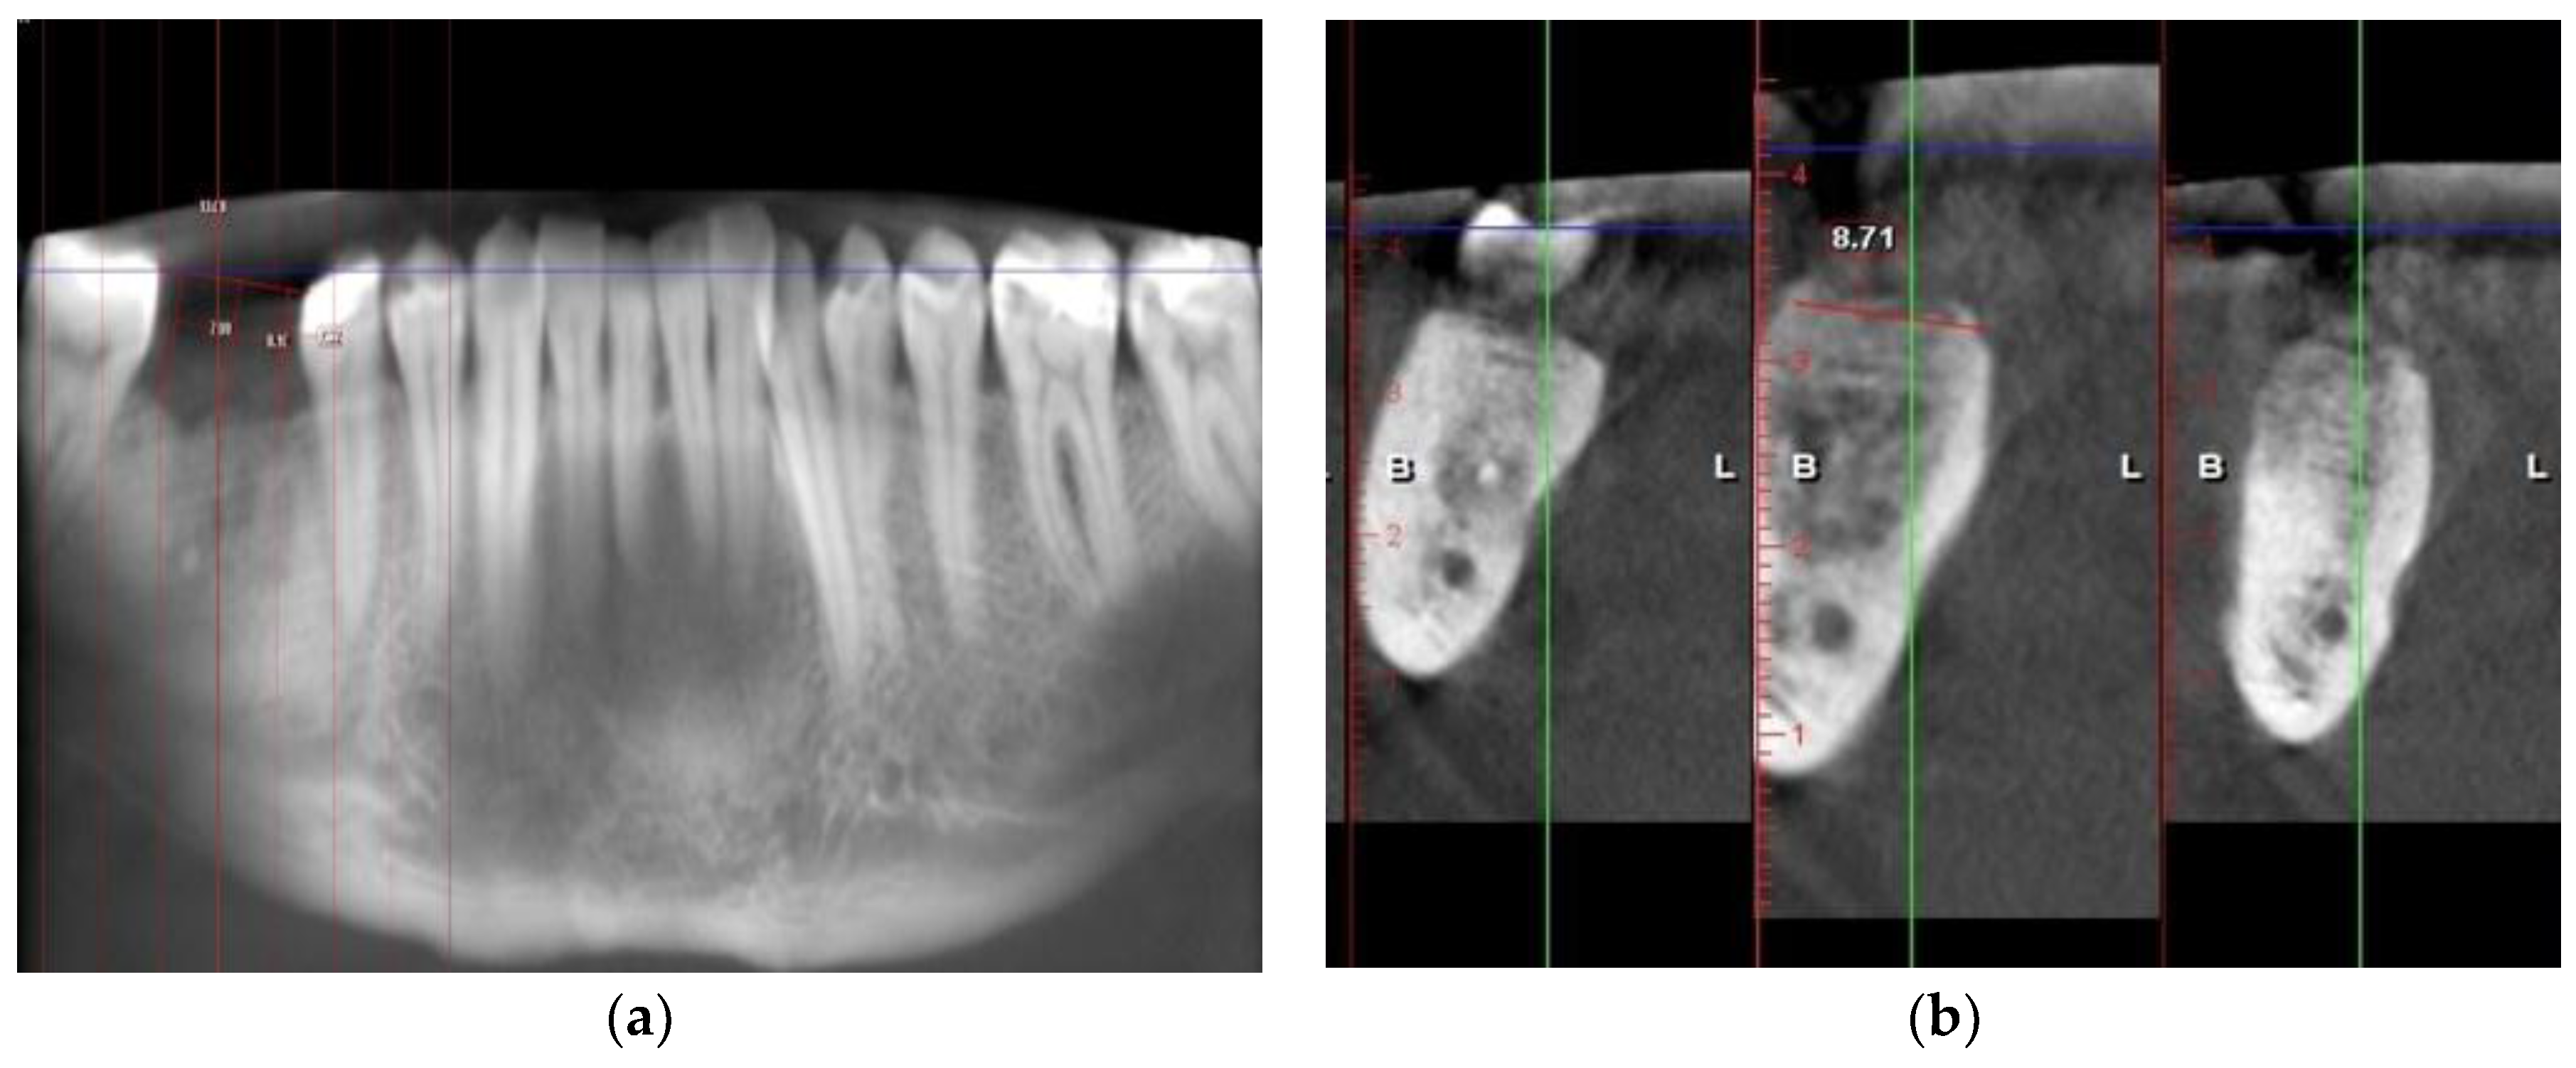

2.5. Radiographic Examination on CBCTs

3.1. Radiographic Analysis